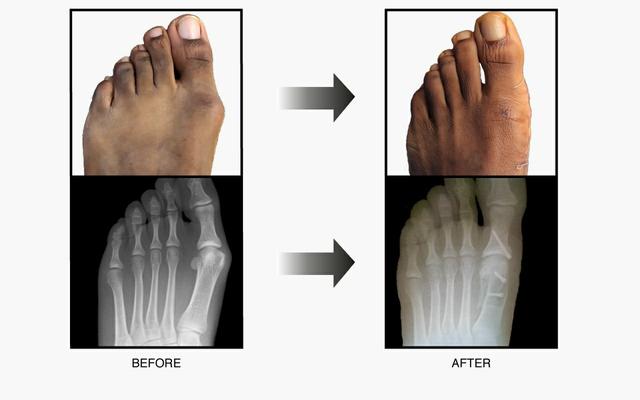

踇外翻叠趾畸形 术前术后 对照图 - 好大夫在线